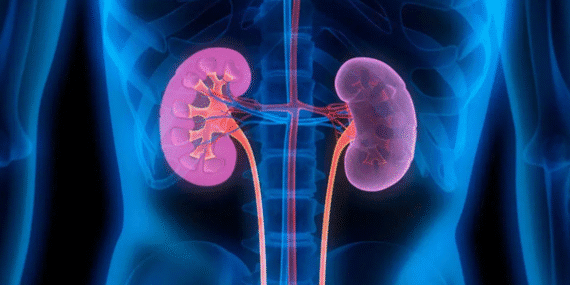

Bilinen en eski böbrek taşı ameliyatı da MÖ 400 yılında yapılmış.

1022 de Alman İmparatoru 2. Henri’ye, Monte Cassino manastırından alınan bir rahip tarafıdan böbrek taşı ameliyatı yapılmış. İmparator, böbreğinin 2 sene sonra tekrar taş yapması sonucu ölmüş.

1520’ye kadar uygulanan cerrahi yöntemlerde bir farklılık olmamış. Sonrasında da böbrek taşı amaliyatlarında yüksek ölüm oranı bilinen bir risk olarak kalmış.

1953’de ilk ultrasonik böbrek taşı kırma işlemi gerçekleştirilmiş. Ses üreten probe aşırı ısındığından etrafındaki dokuyu yakıyormuş.

İlk vücut dışından gönderilen şok dalgaları ile böbrek taşı kırma işlemi 1980’de Münih Üniversitesi Hastanesinde başarılmış.